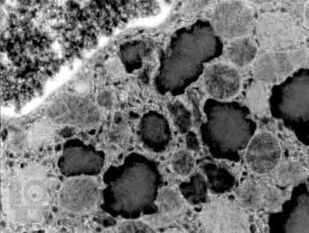

Патология служит своеобразным мостом, объединяющим базовые науки с клинической медициной, и выступает в качестве одной из научных основ для более глубокого понимания болезней. Современная патология активно использует в своем арсенале последние достижения клеточной и молекулярной биологии для всестороннего изучения структурных, биохимических и функциональных изменений клеток, тканей и органов, лежащих в основе различных заболеваний.

Выявленные патологом изменения находят свое отражение в нарушениях на глубинном уровне функционирования клеток, внеклеточного матрикса, субклеточных структур, на уровне повреждения тканей, и в итоге формируют симптомы и синдромы у пациента. Так понимание причин, механизмов, морфологических и биохимических связей при повреждении клетки ведет к пониманию клинических проявлений заболеваний и подходов к их лечению.